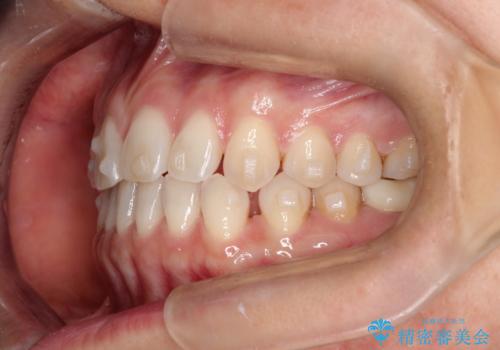

【インビザラインで再矯正】マウスピース矯正で隙間を閉じたい

- 過去に矯正を行ったあと、前歯の後戻りを主訴に来院されました。

マウスピース矯正にて隙間を閉じる計画をたて、治療を行いました。